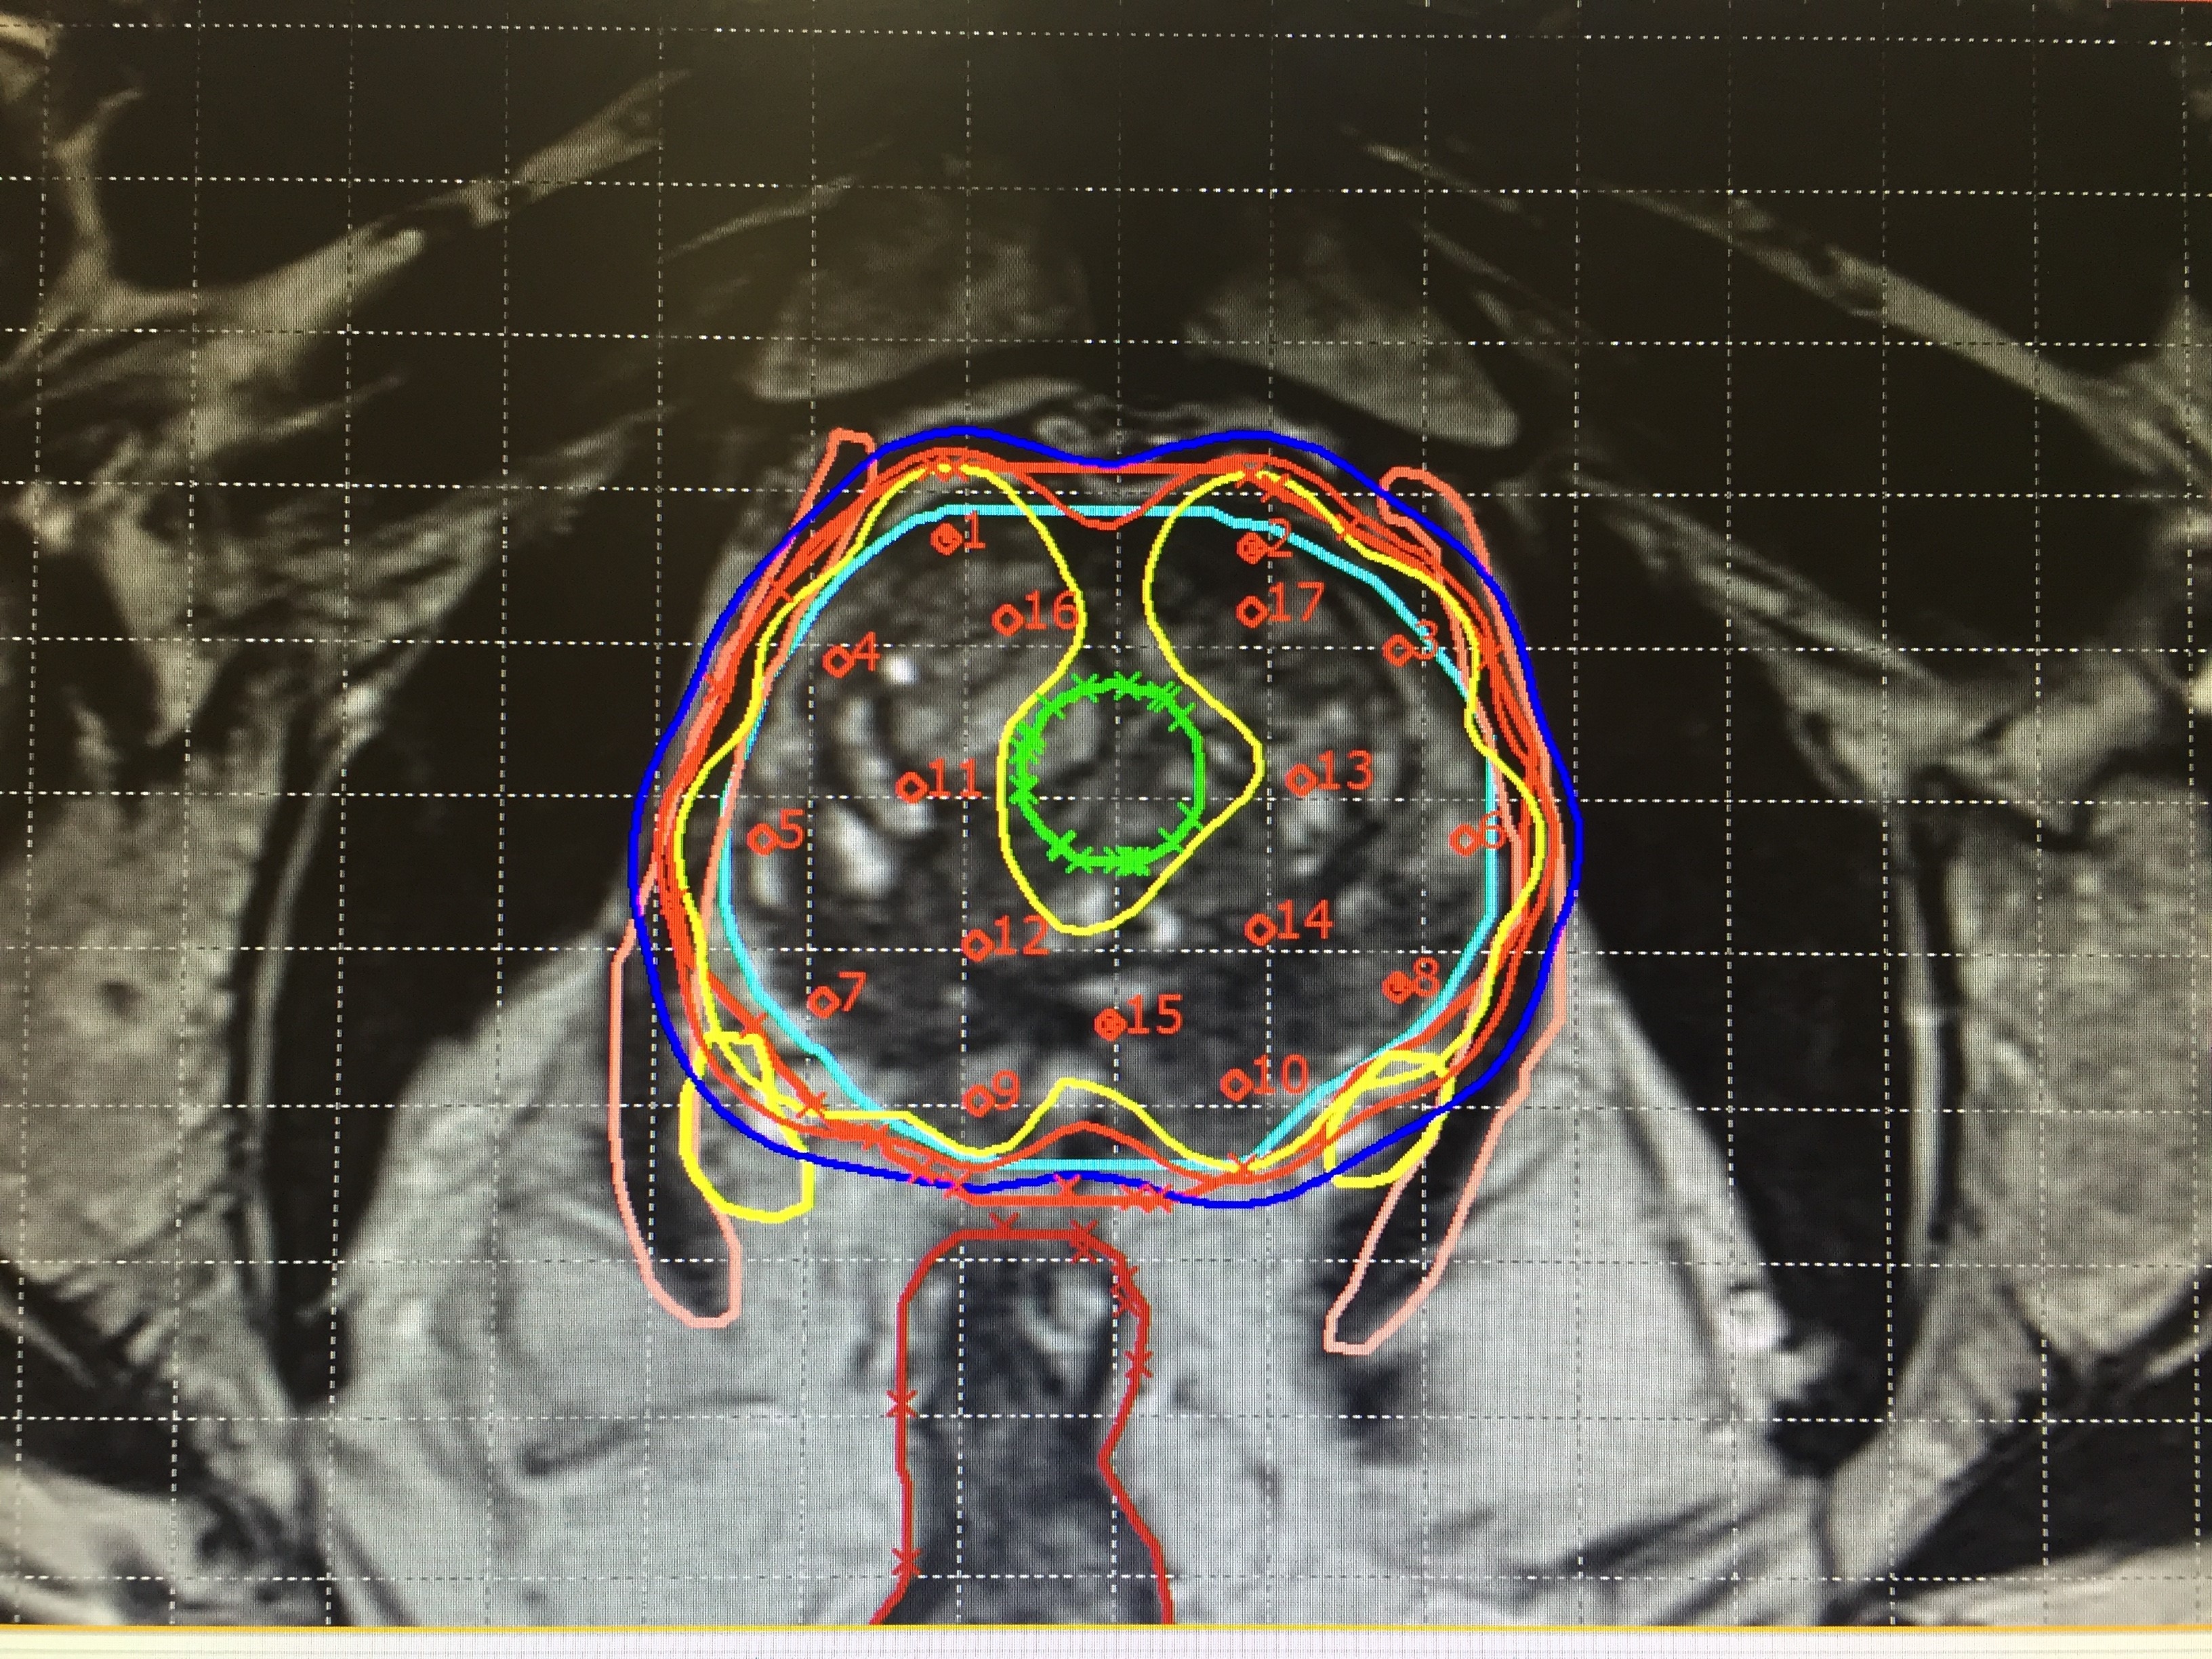

Treatment planning

Imaging is used for treatment planning: from medication and radiotherapy to surgery or, in certain cases, palliation. During radiotherapy planning, medical imaging generates three-dimensional images of the tumour, allowing for better radiation therapy targeting of the tumour while minimising damage to healthy tissues.

Image-Guided Radiotherapy (IGRT) incorporates real-time medical imaging into the radiotherapy process to ensure accurate and consistent delivery of radiation doses.

igbt-scifobulletin2019-contouringandplanning.jpg

Detailed medical images enable health professionals to distinguish between tumours, healthy tissues and organs to ensure cancer cells are correctly targeted. (Photo: Auna Oncosalud)